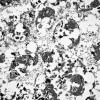

8I3 Granular Cell GBM (Case 8) EM 019 - Copy